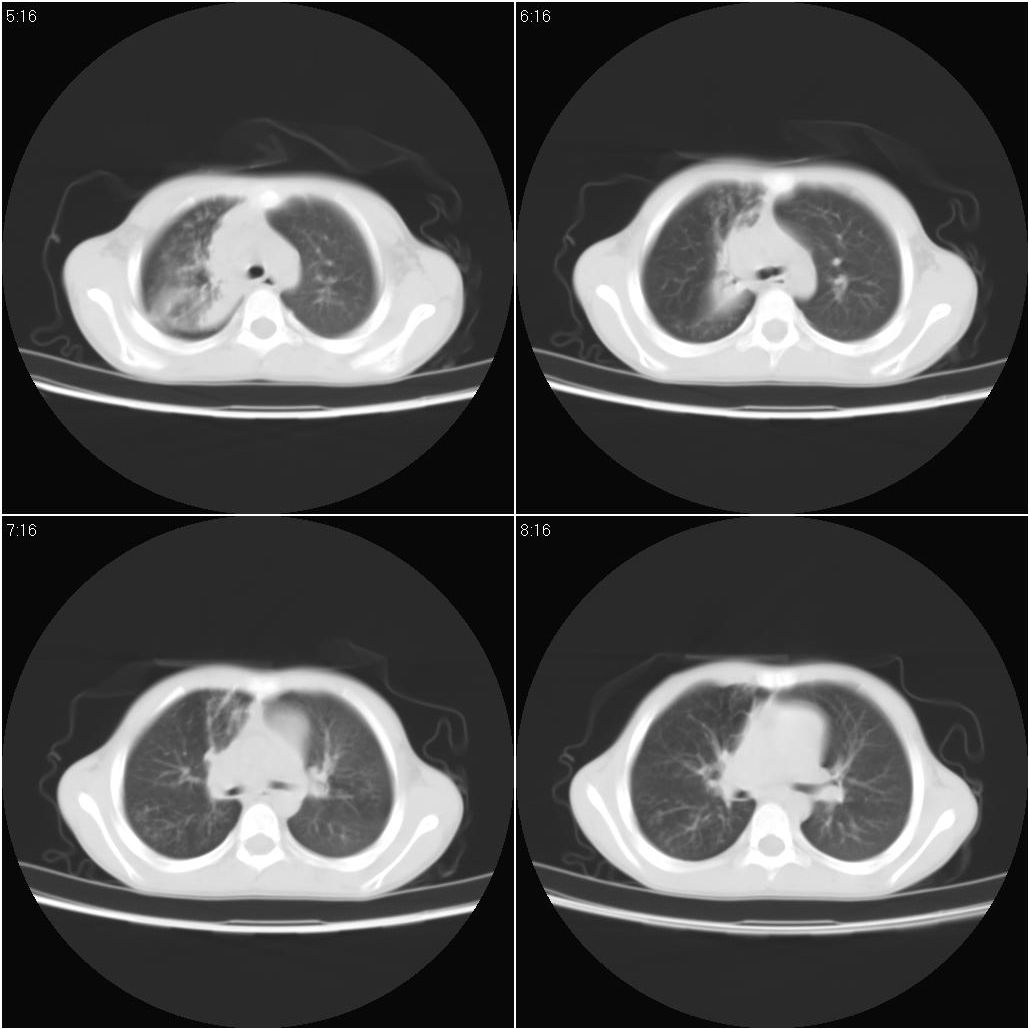

9月8号平片检查情况:

9月15号平片检查情况:

9月20号平片检查情况: